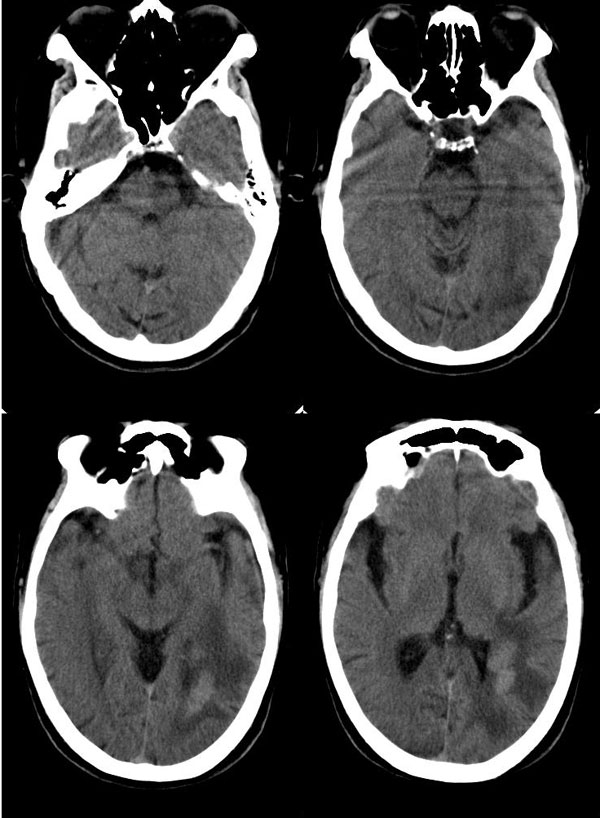

病人头晕12天,无视力障碍及肢体活动障碍

病灶平扫ct值约38hu,强化后明显强化,ct值约63hu,有一层ct值约72hu,病史:病人,男75,血压120/75,不高,头晕12天,平时体健,当时曾作胸x线片,正常。腹部ct,肝多发囊肿。经治疗(林格液+甘露醇)未用营养液及化疗药,当时诊断转移瘤。12天复查片如下

平扫:左侧颞枕叶内(左侧脑室后角旁)片状或楔形低密度影,内见条片状略高密度影,脑室无受压征象.

增强:条片状影均匀强化.

意见:考虑左侧颞枕叶梗塞.

左颞枕部脑梗塞并少量出血.